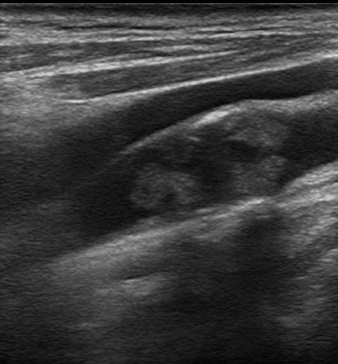

Transcranial Doppler (TCD) and Carotid Duplex Ultrasound (CUS)

Vascular Neurology & Neurovascular Ultrasound